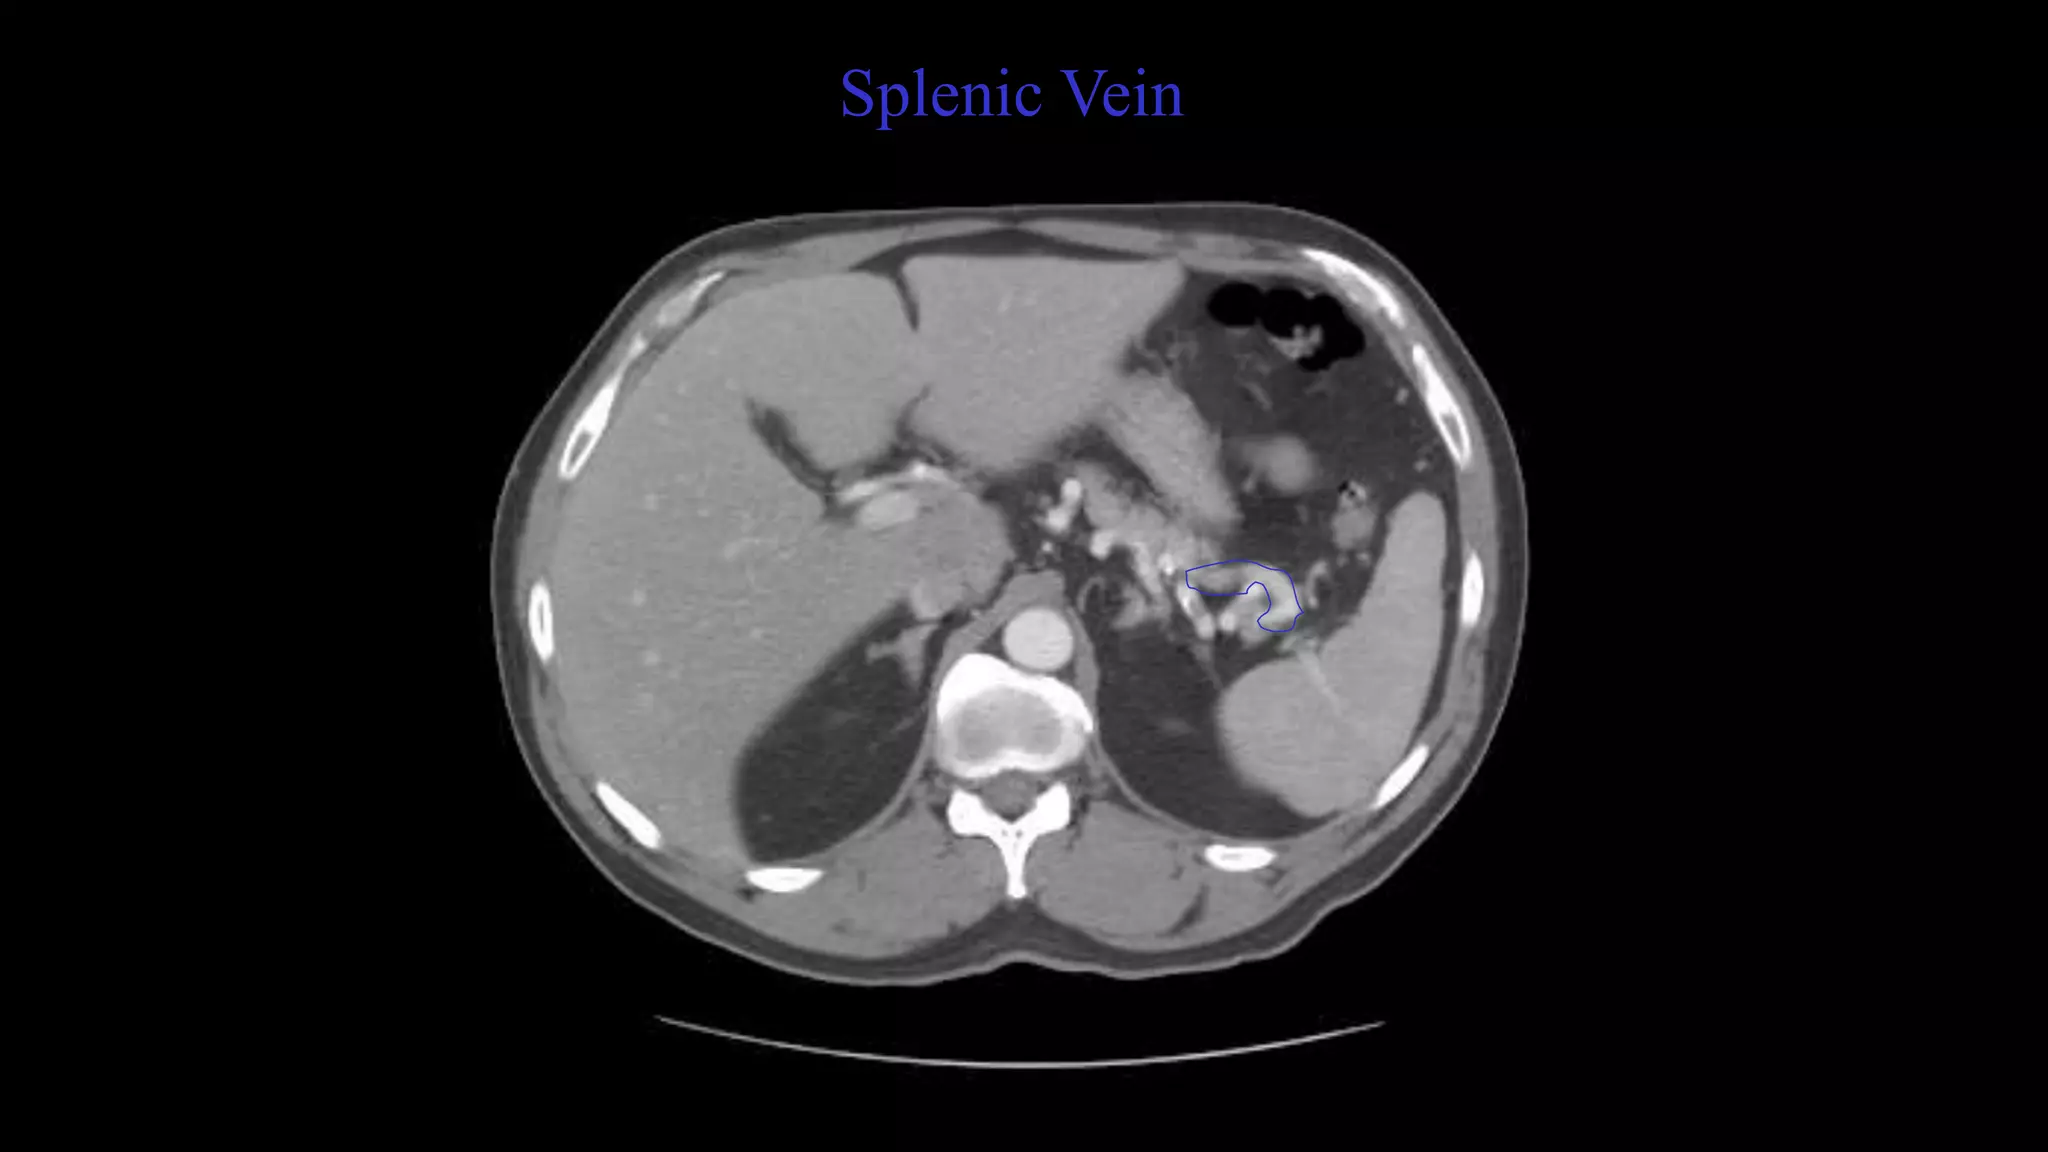

Splenic Artery. Splenic Vein. Scroll up and down

to confirm.

Splenic Vein

Proper Hepatic Artery. Splenic Vein

Here the Splenic Vein is emptying into the portal vein.

Follow this up and down.

Splenic Artery. SplenicVein. Scroll up and down to confirm. Spleen

• 24.

Here the SplenicVein is emptying into the portal vein. Follow this up and down. Pancreas